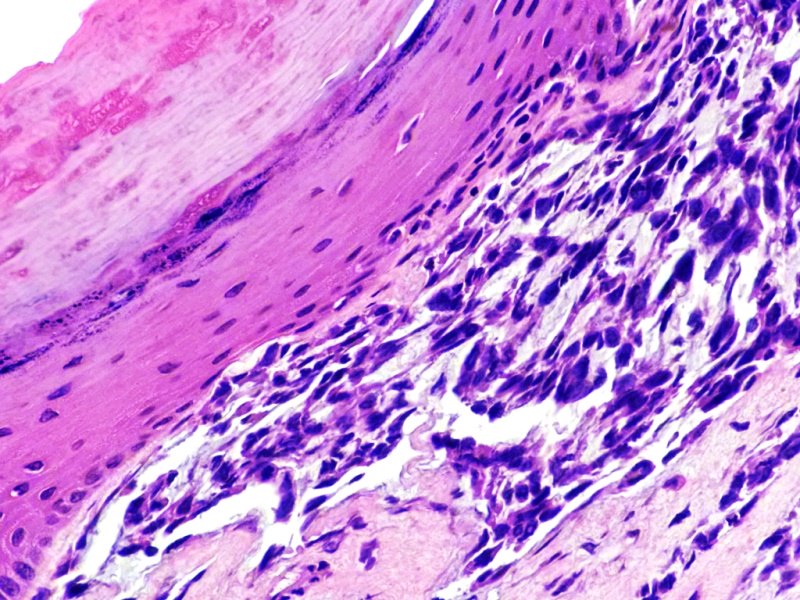

Cérvix uterino. Zona de transformación con carcinoma epidermoide in situ. Tinción HE